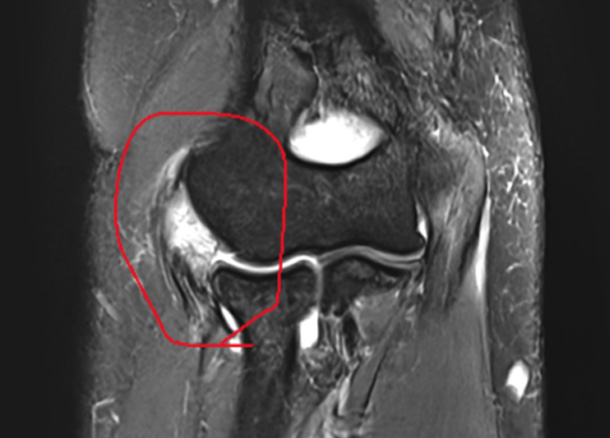

Before 수술 전